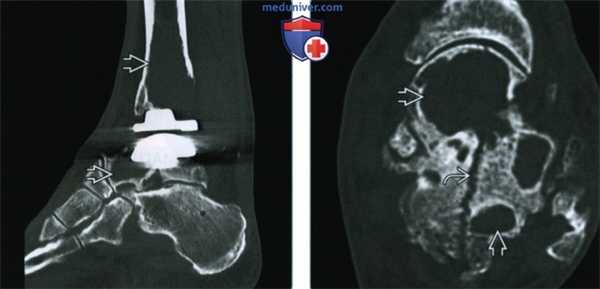

(Слева) КТ кости, сагиттальный срез, этот же случай: отмечается большая чувствительность КТ по сравнению с рентгенографией при визуализации распространенности литических очагов. Обратите внимание, что полиэтиленовый компонент выглядит симметричным, нет признаков его износа.

(Справа) Аксиальная КТ, этот же случай: визуализируется источник инородных частиц, приводящих к массивному остеолизу. Срез выполнен сразу ниже пластины, фиксирующей имплант таранной кости; перелом развивается из этой области высокой нагрузки. Хронический перелом является источником костных обломков, что приводит к массивному остеолизу и нарушению функции.

(Справа) Рентгенография в боковой проекции, этот же случай: осложнения в виде образования мягких тканей позади протеза и лизис большеберцовой и таранной костей. (Слева) КТ кости, сагиттальный срез, этот же случай: отмечается большая чувствительность КТ по сравнению с рентгенографией при визуализации распространенности литических очагов. Обратите внимание, что полиэтиленовый компонент выглядит симметричным, нет признаков его износа.